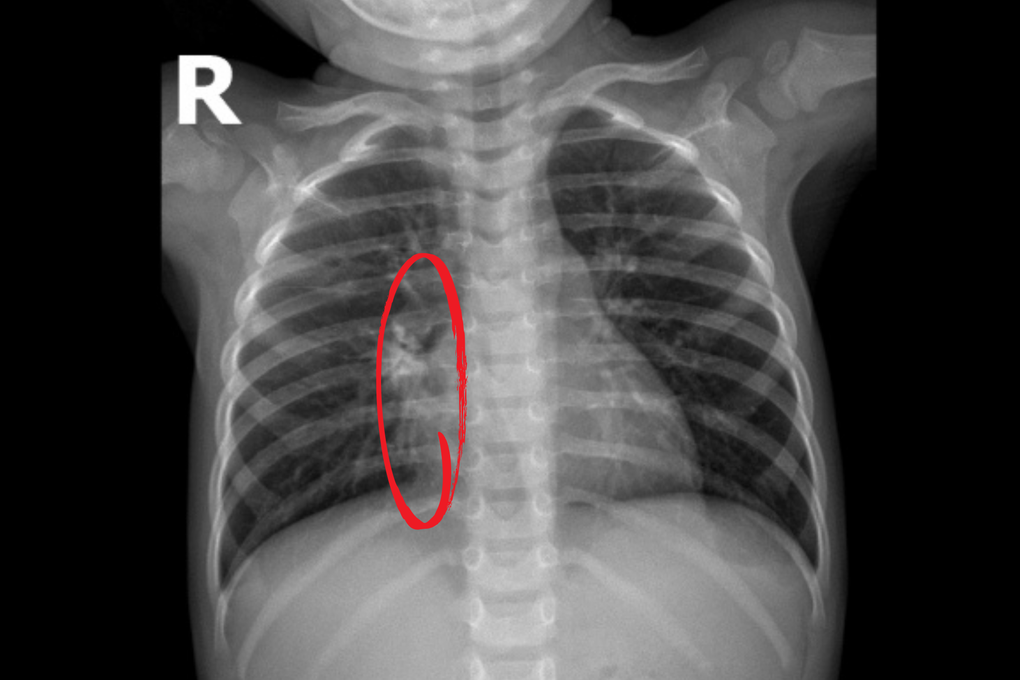

Các kết quả cận lâm sàng được thực hiện ngay sau đó cho thấy tổn thương phổi nghiêm trọng, chụp CT và siêu âm lồng ngực ghi nhận hình ảnh viêm phổi hoại tử với ổ tổn thương kích thước 40 x 42 x 20mm, chiếm khoảng 1/4 phổi phải; tràn dịch màng phổi hai bên dày khoảng 11mm và xẹp hoàn toàn hai thùy dưới của phổi. Nội soi tai mũi họng ghi nhận viêm tai giữa ứ mủ hai bên. Xét nghiệm vi sinh cho kết quả dương tính với RSV và phế cầu.

Kết quả CT và siêu âm ngực cho thấy bé N.P bị hoại tử phổi phải kích thước 40 × 42 × 20mm kèm tràn dịch màng phổi hai bên, dày 11mm (Ảnh: BVCC).